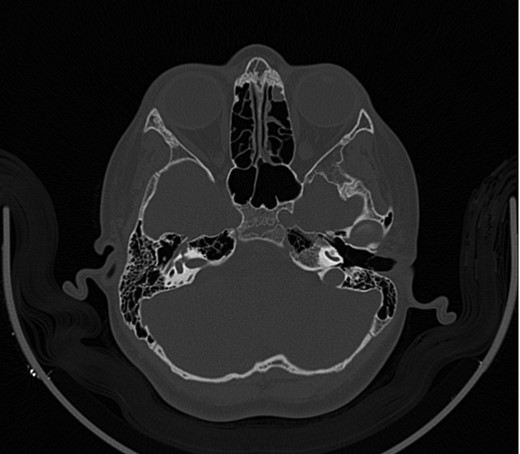

A 14-year-old male patient presented to the ENT clinic with bilateral hearing loss with no other otolaryngological symptoms. History from the patient stated a road traffic accident (RTA) 12 months ago. Meanwhile, the patient had no hearing problems prior to the RTA. Furthermore, detailed history of the accident revealed that the patient had no apparent skull injuries while pure tone audiometry (PTA) on presentation revealed bilateral conductive hearing loss and auditory brainstem response revealed right mild hearing loss and left moderate hearing loss. As a result, he was fitted with hearing aid for four months after presentation and was not compliant to it on the long-term. The patient is a non-smoker and is medically free with normal developmental milestones and negative family history of hearing complaints. Local examination of the ear revealed intact but minimally retracted tympanic membrane bilaterally. PTA was done in 2014 revealed right mild to moderate mixed hearing loss and conductive hearing loss at low frequency (Table 1). Meanwhile, the left ear had mild to moderate sensory hearing loss at high frequency (Table 2). The speech audiogram results show equal canal volume in both ears, less tympanometry pressure on the right ear and less compliance on the right ear (Table 3). The CT showed that both ossicular chains are deranged, and bilateral abnormal ossicles with no fracture or mass (Figures 1–3).

Figure 2:

CT mastoid, deranged right side ossicular disruption.